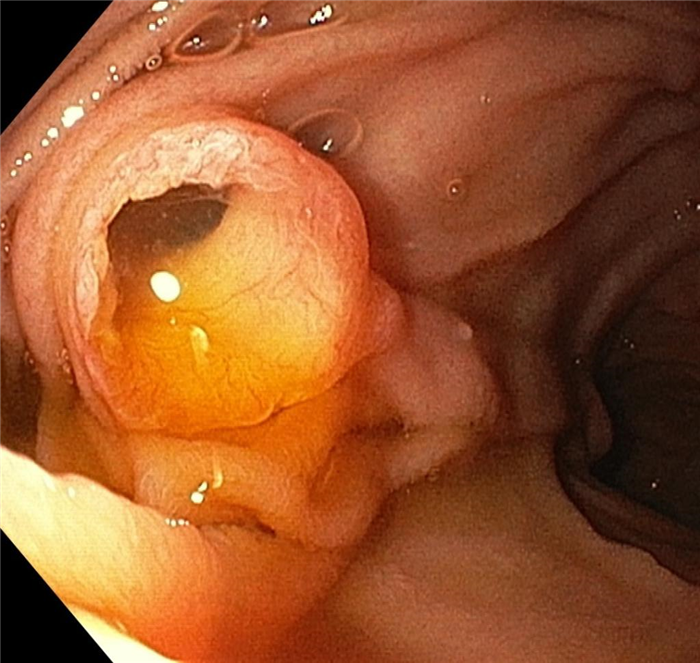

Инвертированное, отечное устье червеобразного отростка в просвет слепой кишки при аппендикулярном инфильтрате